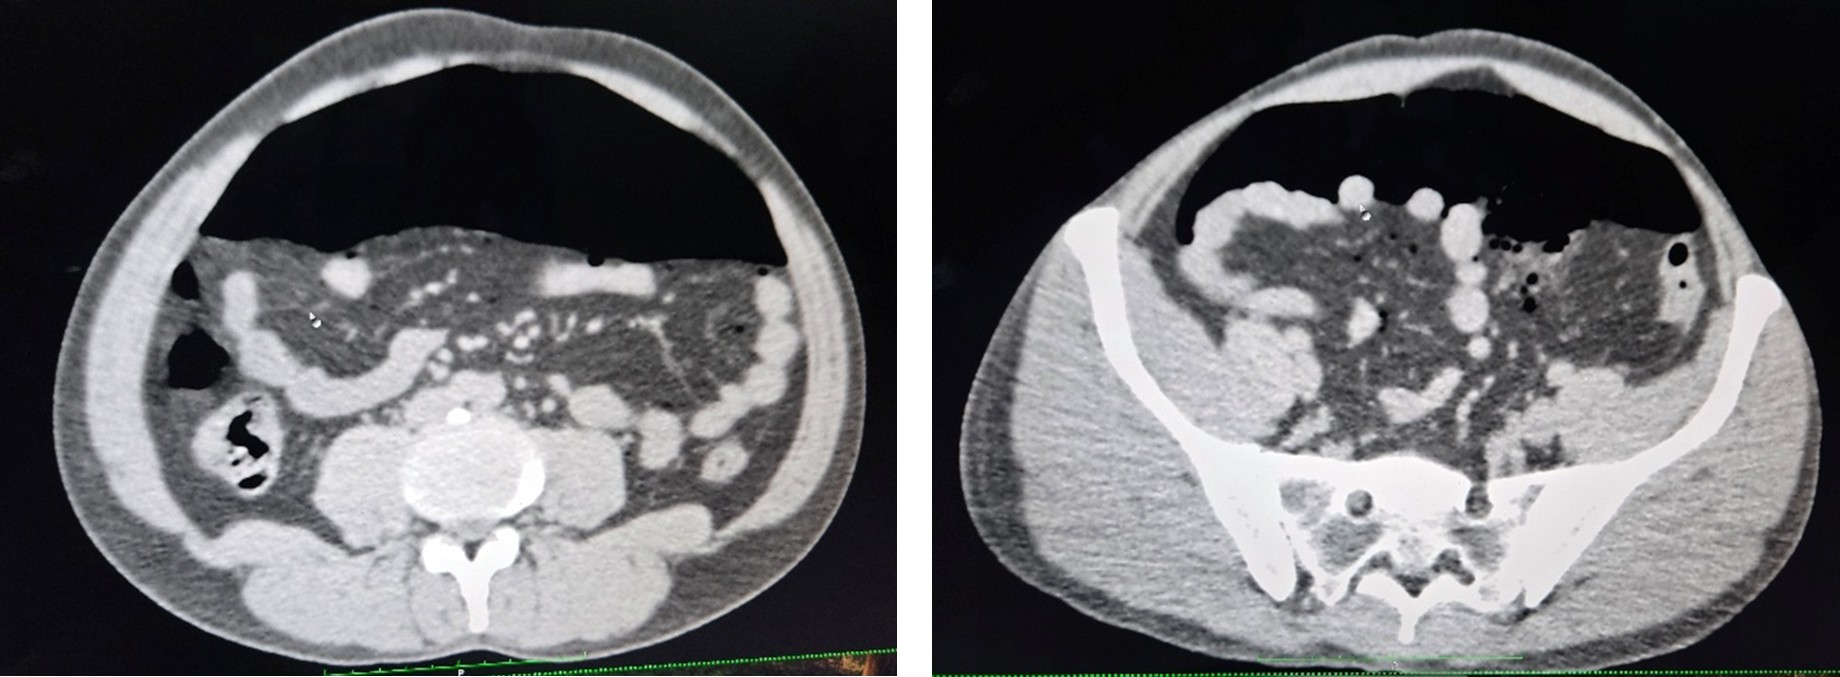

CT Report

CT abdomen revealed colon perforation with intestinal obstruction, requiring emergency surgical management.

Pre Operative

Post Operative

Early diagnosis relies on clinical assessment and radiological imaging, particularly CT abdomen, which helps identify bowel perforation, pneumoperitoneum, and intra-abdominal contamination. In cases of multiple bowel perforations or extensive contamination, emergency laparotomy with bowel resection and colostomy formation is often required.

In the present case, the patient sustained multiple perforations involving the sigmoid colon, descending colon, splenic flexure, and distal transverse colon, necessitating left colon resection and end colostomy. Postoperatively, the patient developed intestinal obstruction due to internal herniation, which required re-exploration surgery. Timely surgical intervention and close postoperative monitoring played a crucial role in preventing further complications and ensuring patient recovery.